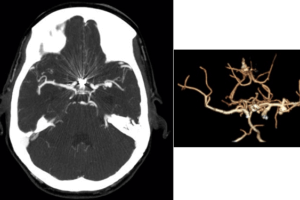

MCA aneurysm

History : 45 year old man with sudden onset of severe headache. What is the most likely etiology for this patient’s intraventricular hemorrhage? Read more »